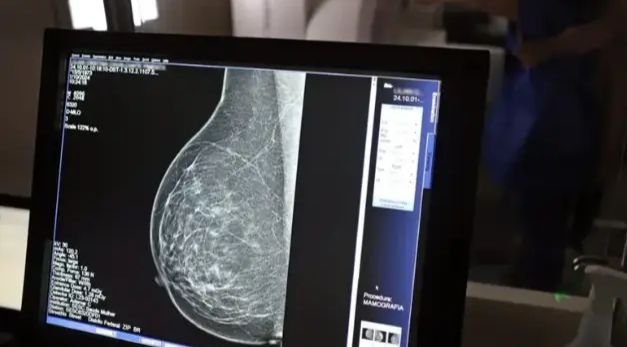

Faixa etária da mamografia é ampliada no SUS; exame passa a ser indicado até os 74 anos

O Ministério da Saúde (MS) anunciou nesta terça-feira, 23, a ampliação da faixa etária para o rastreamento do câncer de mama no Sistema Único de Saúde (SUS). A partir de outubro, o exame passará a incluir mulheres de 50 a 74 anos. Antes, o limite era de 69 anos. A novidade faz parte de uma série de novas recomendações para a detecção precoce da doença.